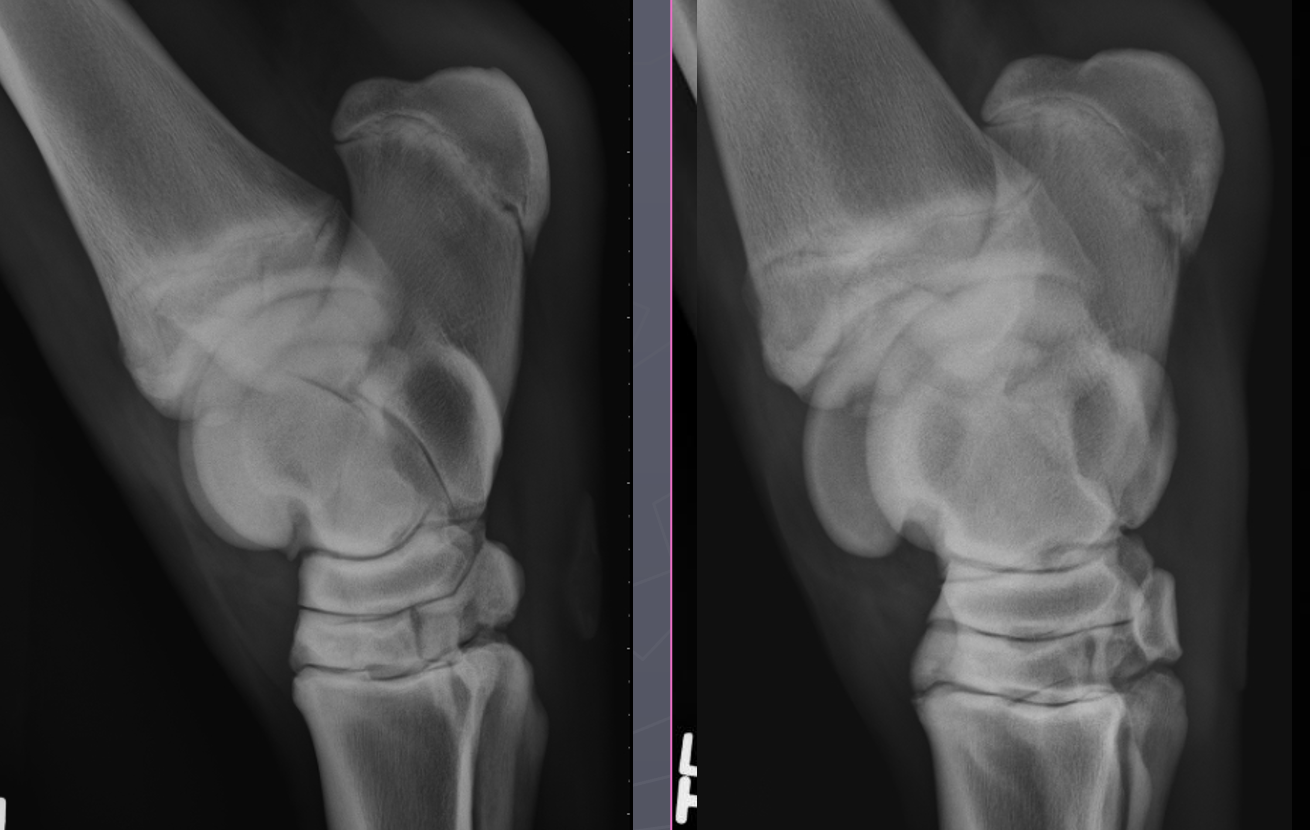

What is shown in these images?

physeal septic arthritis and osteomyelitis -lots of swelling

physeal septic arthritis and osteomyelitis -more focal lesion -asymmetrical swelling